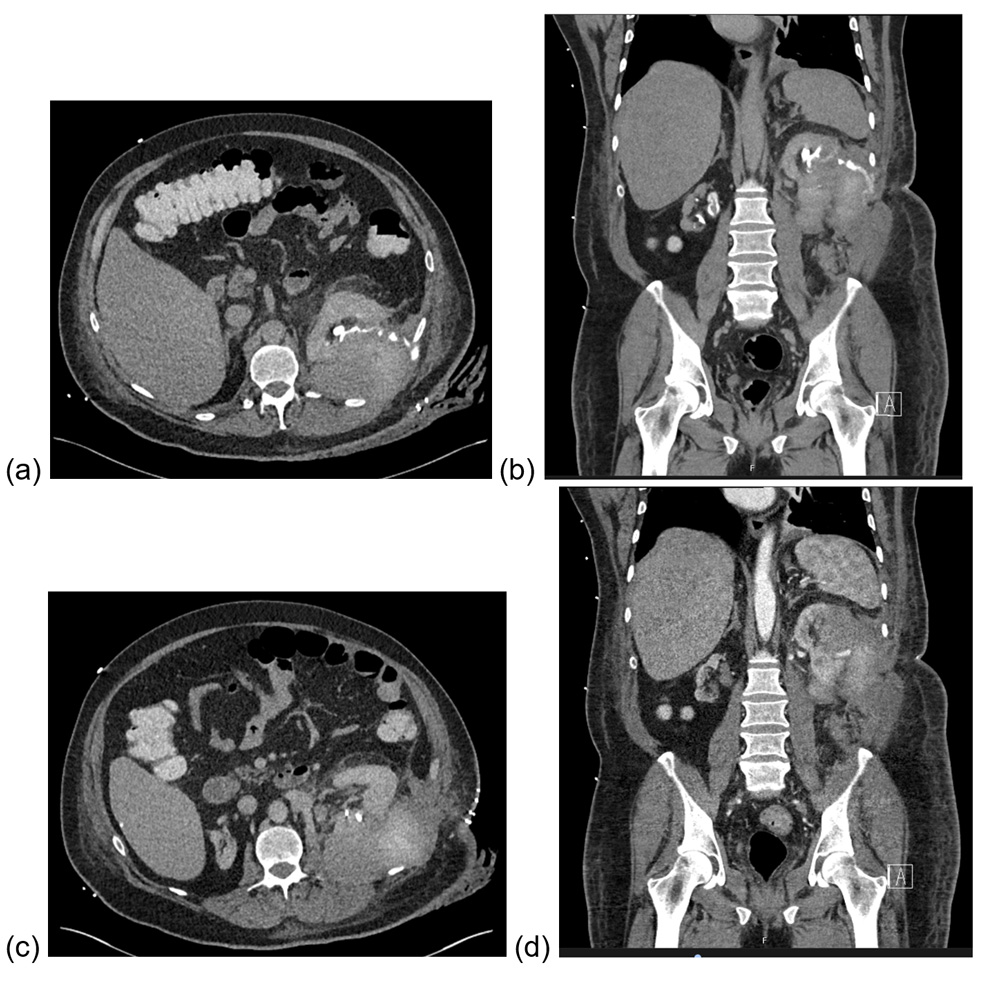

Figure 3: CT (axial and coronal) showing urinoma (a, b) + persisting pseudoaneurysm (c, d).

In ICU he continued to require blood transfusions, started spiking fevers, and had ongoing fluid leak from his wound. Repeat CT with a delayed phased showed persisting contrast in the aneurysm despite embolisation, and contrast leak from the collecting system (Figure 3). He was transferred to our department and underwent a repeat angioembolisation, retrograde pyelogram and insertion of ureteric stent (Figure 4). A circumcision was also performed, with histopathology confirming lichen sclerosus. He was discharged eight days after transfer, with a plan to remove the urethral catheter and ureteric stent at three weeks and three months respectively.